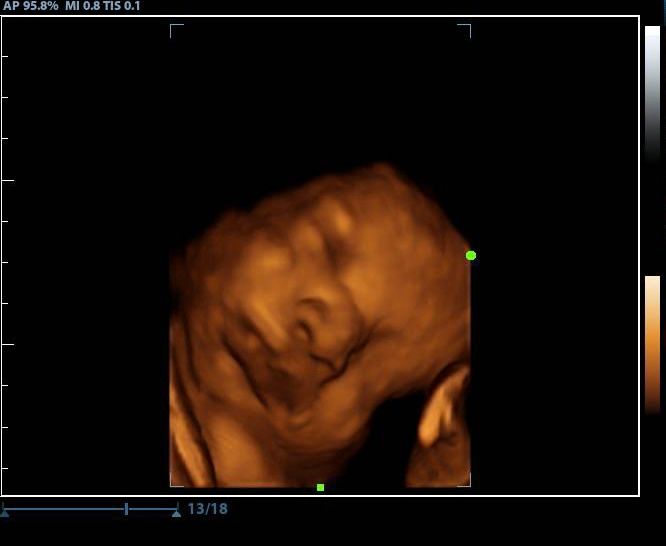

2d, 3d,4d & HD live

In Home 3d/4d Ultrasound

Enjoy a private, affordable ultrasound from the comfort of your home, perfect for moms between 7–41 weeks. Share the moment with loved ones by connecting directly to your TV for real-time viewing in 2D, 3D, or 4D. Ideal for baby showers or gender reveal parties!

• 20- 40 minute in-home session

• Gender determination (14+ weeks)